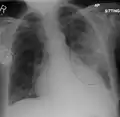

Double pneumonia (bilateral pneumonia)

This is a historical term for acute lung injury (ALI) or acute respiratory distress syndrome (ARDS).[15] However, the term was and, especially by lay people, still is used to denote pneumonia affecting both lungs. Accordingly, the term 'double pneumonia' is more likely to be used to describe bilateral pneumonia than it is ALI or ARDS.